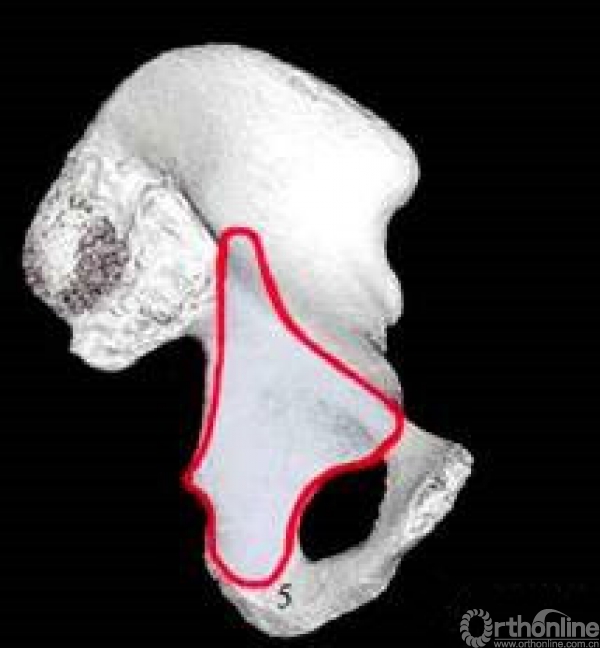

五个手术窗口

窗口5:与窗口3类似,但位于真骨盆深面,可暴露方形区和坐骨棘。可从内侧进行钢板的置放。

五个窗显露区域